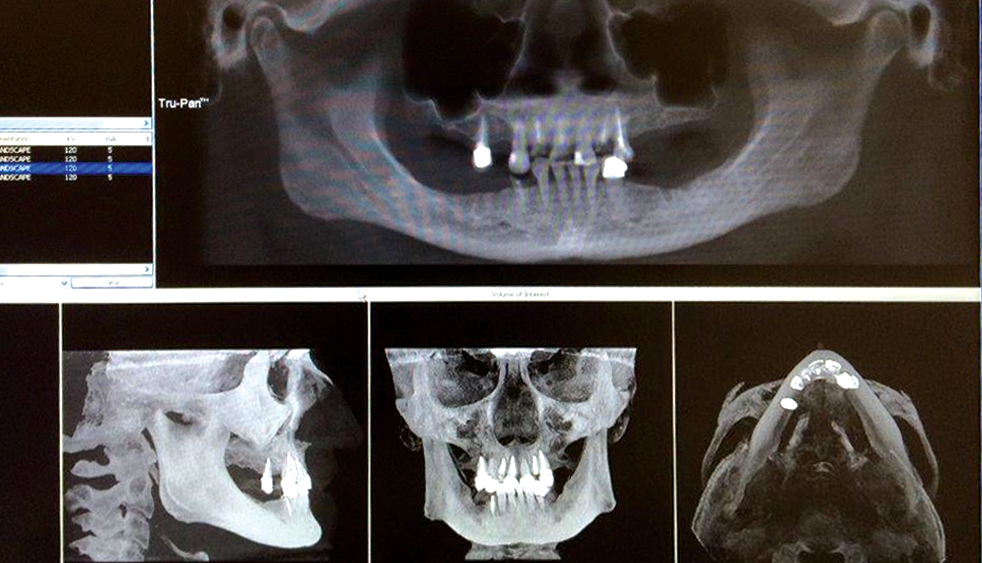

A patient sought treatment for advanced caries and periodontal disease in the maxillary arch, which had become painful and compromised her oral function. Although her remaining mandibular teeth also required replacement, she couldn’t afford to restore both arches at once and, like most patients, she placed a higher priority on her maxillary arch because of her esthetic needs. Following a discussion of treatment options, the patient requested a fixed restoration and was opposed to a removable appliance. At the surgical appointment, her maxillary teeth were extracted and Hahn™ Tapered Implants (Glidewell Direct; Irvine, Calif.) were placed. Sufficient primary stability was established for an immediate provisional appliance, which satisfied the patient’s request to leave the surgical appointment with a fixed restoration in place. After five months of healing and confirmation of the prosthetic design with a PMMA provisional, function, esthetics and quality of life were restored with a BruxZir Full-Arch Implant Prosthesis.